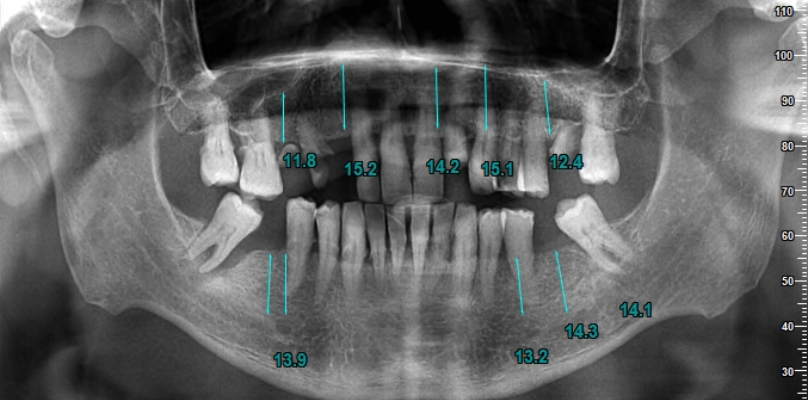

La première étape du processus de traitement consiste à prendre des images radiographiques détaillées. Ces images aident à déterminer le plan de traitement le plus approprié en évaluant la structure de votre mâchoire et votre santé dentaire. Nos radiographies révèlent à quel point le processus de traitement est extrêmement minutieux.